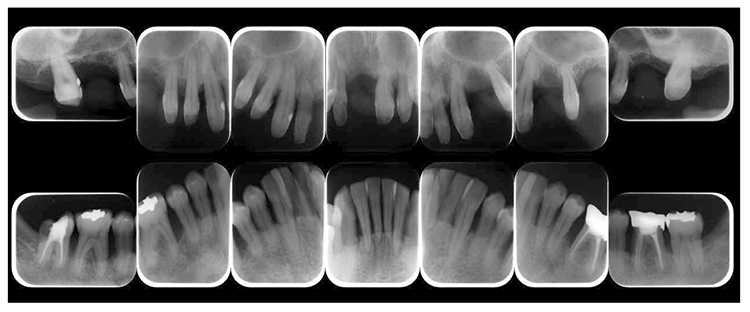

(3) X-ray findings

At the first visit, the findings showed moderate to advanced horizontal alveolar bone resorption in the entire jaw, and advanced vertical bone resorption on 24,36,46, 47. Additionally, on 46,47 were radiolucent findings that were likely associated with furcation involvement, and radiolucent areas on the alveolar bone surrounding the root apex were shown on 16,11,26. Furthermore, distally on 47, radiolucent findings showed caries extending into the dental pulp.(Fig.1c).

Fig 1c

(Fig.1c) Dental X-ray 14 during first visit (June 2007)